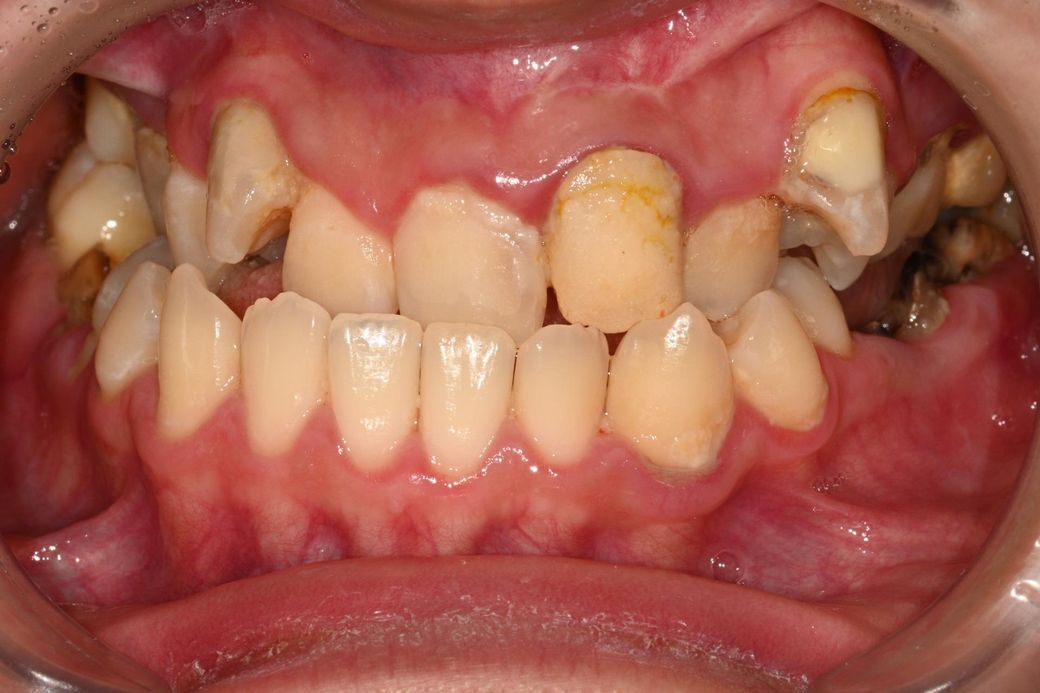

양악수술 건강보험 적용 가능한지 알려주세요.

상하악 중절치 치간선의 어긋남으 10mm이상에 해당하는지 육안으로 봤을때 어느정도인지 알려주세요..

육안으로 보기에는 심한 편이라 의료보험 적용될 가능성 높습니다. x-ray 소견도 보아야 합니다.

사진으로 봐서는 대략적으로밖에 볼 수 없는데요, 일단 정중선이 꽤 틀어져 있고 교합되는 치아도 적어서 부정교합이 심한편이긴 합니다

덧붙이자면, 교정도 교정인데 치주치료, 충치치료가 우선일 것 같습니다